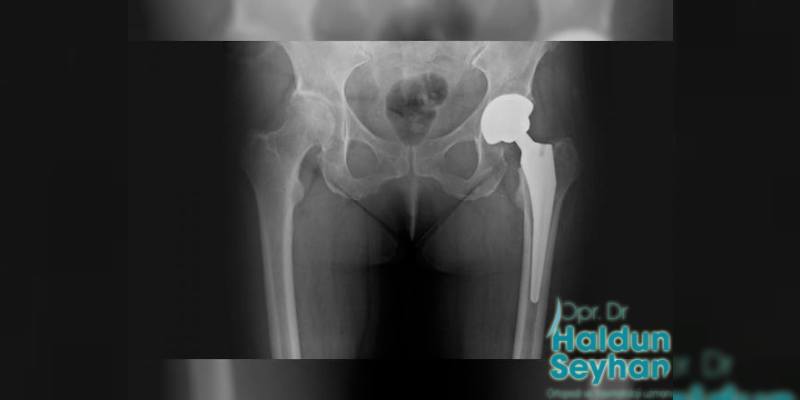

Kalça protezi, çeşitli sebeplerle bozulma yaşanmış eklem yüzeyine yerleştirilen, kobalt-krom veya titanyumdan oluşan ana parçalar olmak üzere, bu parçaların eklemleştiği yerde polietilen, metal ya da seramik parçalardan oluşmaktadır.

Kalça Protezinin İşlevi ve Uygulanması

Kalça protezlerinin uygulanması durumunda başarılı sonuçlar alınabilmesi için bir diğer önemli durum hastaya uygun protez seçimidir. Hastanın eklemlerinde meydana gelen deformasyonların en doğru şekilde tanılanması ve hastanın detaylı şekilde tetkiklerden geçirilmesi, uygulanacak olan kalça protezinden başarılı sonucun alınması ve hastanın iyi şekilde tedavisinin gerçekleştirilmesi açısından önemlidir.